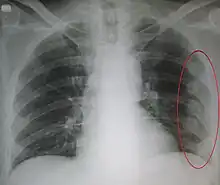

Since most causes of pediatric and adolescent chest pain are not considered life-threatening, parents and their children are often reassured that in the majority of cases, the cause of the pain can be determined. If the child or adolescent appears to have some dehydration, and intravenous line along with administration of saline is done. The clinician may or may not decide to perform diagnostic testing . This is especially true if the child or adolescent has symptoms of chronic pain. If an obvious cause of the chest pain is not readily apparent, testing may begin with an x-ray and an electrocardiogram . This helps the clinician to determine whether or not the cause of pain is related to pulmonary or cardiac causes.[4]

- subcutaneous emphysema can be felt by the clinician indicating a pneumomediastinum or pneumothorax

- Pneumothorax